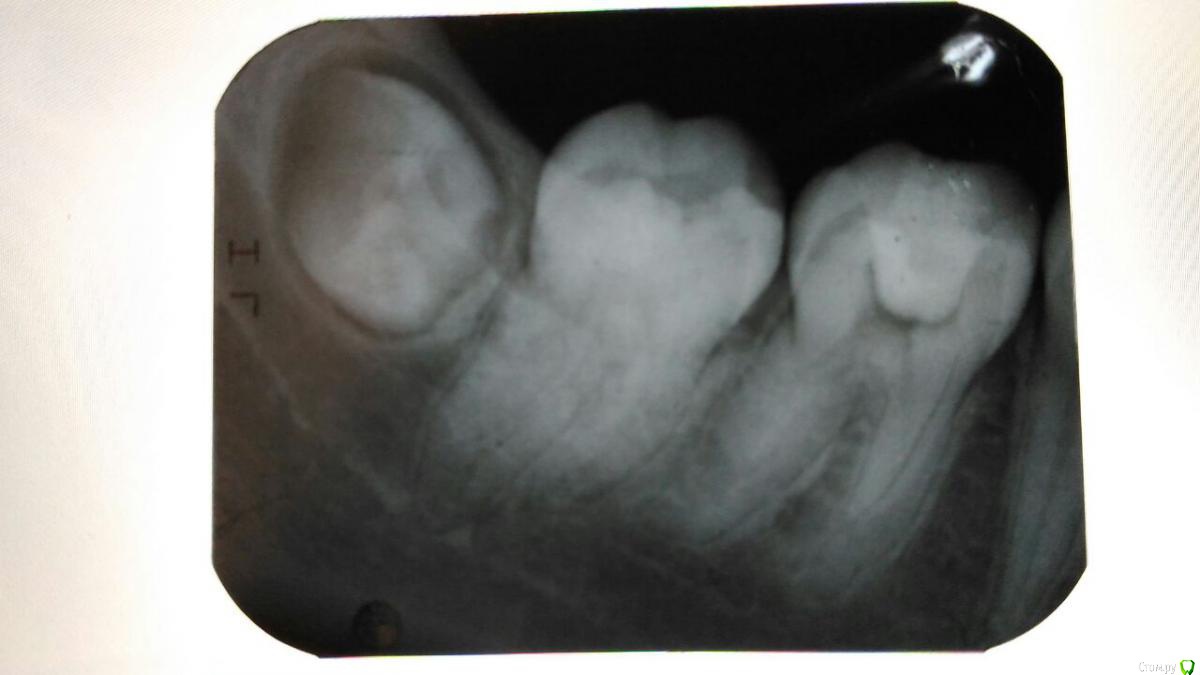

Katerina99 Опубликовано 27 декабря, 2016 Поделиться Опубликовано 27 декабря, 2016 (изменено) Здравствуйте, мне врач лечил зуб и выписал направление на рентген. Что можете сказать о состоянии шестерки и соседних зубов? http://radikal.ru/fp/86ubig91pn2bh Изменено 27 декабря, 2016 пользователем Katerina99 Ссылка на комментарий

Katerina99 Опубликовано 27 декабря, 2016 Автор Поделиться Опубликовано 27 декабря, 2016 Вас сейчас что-то беспокоит? По какому поводу направили на снимок? Небольшой дискомфорт есть и привкус лекарств иногда. Завтра я с этим снимком иду на итоговое лечение. В первый раз мне врач ставил временную пломбу, через некоторое время убрал ее, прочистил каналы, чем-то обработал и заделал новой пломбой с условием, что я сделаю рентген и приду на прием. Ссылка на комментарий

Katerina99 Опубликовано 27 декабря, 2016 Автор Поделиться Опубликовано 27 декабря, 2016 А зуб в цвете не изменен? Ну как сказать? Сброку было темное пятно и, как я поняла, на жевательной поверхности вторичный кариес. Врач убил нерв, прочистил каналы, сделал пломбу и сказал, чтобы я к нему со снимком пришла. Ссылка на комментарий

St. Опубликовано 27 декабря, 2016 Поделиться Опубликовано 27 декабря, 2016 По снимку видно пломбу в полости зуба и корневые каналы без контрастного материала. Ссылка на комментарий

St. Опубликовано 28 декабря, 2016 Поделиться Опубликовано 28 декабря, 2016 Что за контрастный материал?Поясню. Сейчас в каналах корня где раньше был нерв или ничего нет или материал не видимый на снимке,т.е.неконтрастный.Когда каналы пломбируйте постоянно их в подавляющем большинстве случаев закрывают рентген контрастными материалами. За счет этого можно увидеть белые полоски на снимке там где раньше был "нерв" Ссылка на комментарий